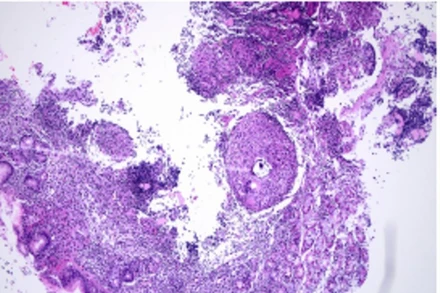

Việt Nam là nước có gánh nặng nấm Aspergillus phổi mạn tính đứng thứ 5 trên thế giới với trên 55.000 ca. Đây là căn bệnh khó khăn trong chẩn đoán, tỷ lệ tử vong cao nhưng chưa được người dân quan tâm.